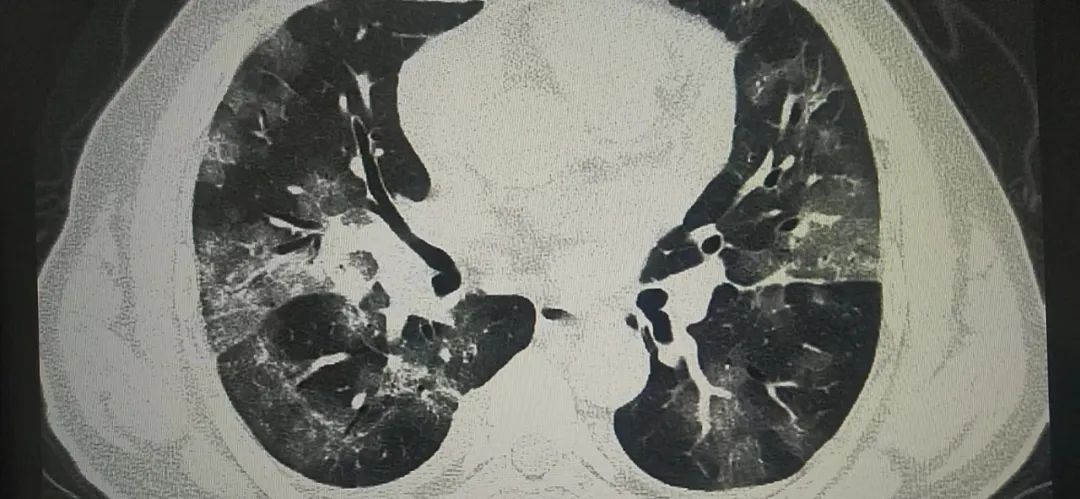

据陕西冶金医院医学影像科付建英主任讲,目前新闻各种报道奥密克戎感染后大部分为无症状或轻症,我自己接诊的患者中一部分有出现肺部表现的患者。比如上面的病例,CT检查都是出现了肺部表现,一个人是病变局限,病变于胸膜下分布。表现为单发或多发磨玻璃样密度结节状、斑片状影。其内可见空气支气管征和血管增粗表现。另外一个则是弥漫性磨玻璃样渗出,病变进展,病灶增多、范围扩大。可累及多个肺叶,下叶居多。病灶变密实。严格意义上讲,这几个病例都倾向于类似于新冠感染后的肺部表现。随着感染人数增多,可能还会有类似的病例出现。好在这样的病例确实不多,大部分还是上呼吸道感染的症状居多,发热咽痛是最常见的症状表现,但如果出现呼吸困难,还是要到医院拍个CT的。

新冠肺炎并不是什么“大号流感”,即便“症状较轻”也千万不能轻视。不要以为新冠只是单纯感冒,上呼吸道感染如果不及时用药,会进展肺部,也会出现阴影。所以当下全面开放后,还是要做好自己是第一健康负责人,带好口罩,注意防护,不要躺平,既不要轻视但也不要过度恐慌,正确对待它。